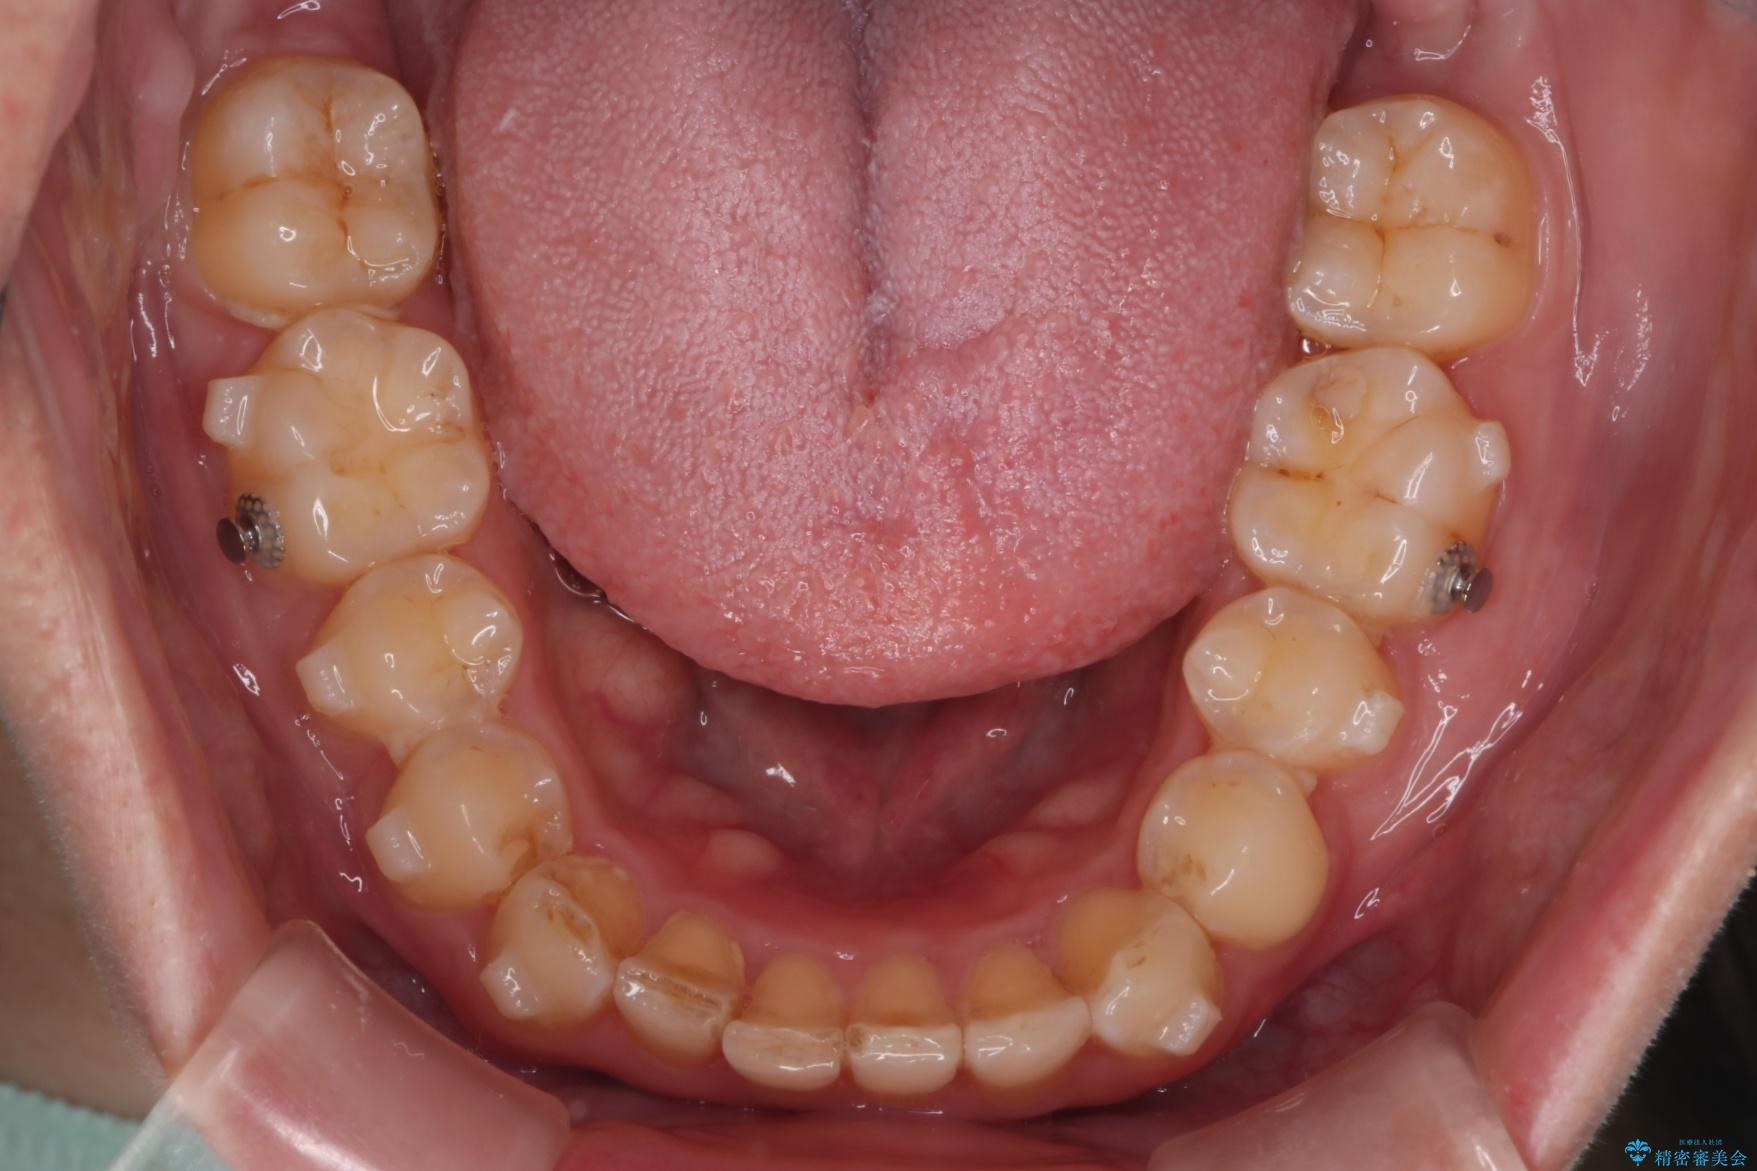

噛み合わせをよくするために、ワイヤー矯正とインビザライン矯正のどちらの期間も必要な箇所にゴム掛けを行いながら治療を行いました。

下の前歯のがたつき改善にはIPR(歯と歯の間を削る処置)を行いました。

ゴム掛けを頑張っていただいたので、噛みあわせも改善され綺麗な歯並びになりました。